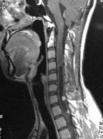

MRI:大部分脊髓肿瘤包括转移瘤的T1加权图像信号减低或不变。T2加权图像则信号增强,但骨母细胞瘤,部分前列胰癌骨转移信号减低。

脊椎X线摄片可能显示骨质破坏,椎弓根间距增宽或椎旁组织变形.脑脊液蛋白定量通常增高.脊腔动力测定显示蛛网膜下腔内存在阻塞现象.如有完全性阻塞,进行腰穿有危险性,应先作成像检查.对脊髓肿瘤MRI能提供确诊,虽然偶尔有需要作CT脊腔造影检查,特别是为确定硬脊膜外的肿瘤.CT脊腔造影术可能提供第一个线索指出病变是动静脉畸形,后者可经选择性动脉造影检查加以证实.